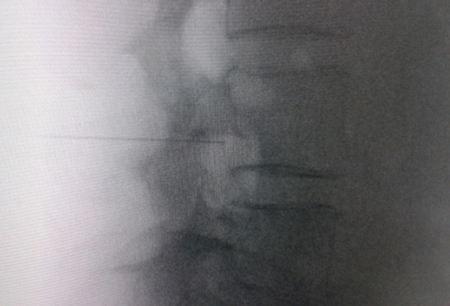

Access by transforaminal route is the most widely used (4). The patient is placed in prone position with an abdominal pillow to reverse physiological lordosis. The most commonly used RF needles or cannulas are 20 or 22 G diameter and 98 mm long with 0.5 or 1 cm active tip. Following asepsis with alcoholic chlorhexidine and placement of sterile fields, radiological approaches in anteroposterior, oblique and lateral incidence are performed. In anteroposterior incidence and moving the arc in cranio-caudal direction, the double arc of the lower vertebral edge is deleted. In oblique incidence between 20 and 30 degrees ipsilateral to the DRG to be treated, the classic image described as “Scotty Dog” will be displayed, which is the result of bringing the articular facets and the spinous process closer to the contralateral side. The entry point will then be immediately below the pedicle. After local anesthesia with 1 % lidocaine, the needle will be inserted following a tunnel vision and will not advance beyond half of the pedicle in this projection to prevent neural injury. In lateral projection, it will be inserted into the roof of the neuroforamen (Figures 1 and 2) but the final location will be determined by sensory-motor nerve stimulation. Sensory stimulation is to cause paresthesia or pain in the affected territory with stimulation between 0.3-0.6 v. During motor stimulation fasciculations can be caused in the affected territory with a voltage of twice that necessary to cause paresthesia. If an intraganglionar denervation, promulgated by some authors, is desired, both sensory and motor stimulation will be positive at less than 0.3 v. As this is a more painful procedure, it is advised to administer local anesthetics after the painful stimulus and before treatment. The impedance should be kept below 450 ohms, which is achieved by infusing saline before proceeding with RF (4). The use of contrast is good practice, as it rules out the intravascular and intrathecal position of the radiofrequency cannula.

Fig. 1. Lateral radiological view showing a radiofrequency cannula at the anterosuperior angle or roof of the neuroforamen, approximate topography of the dorsal root ganglion